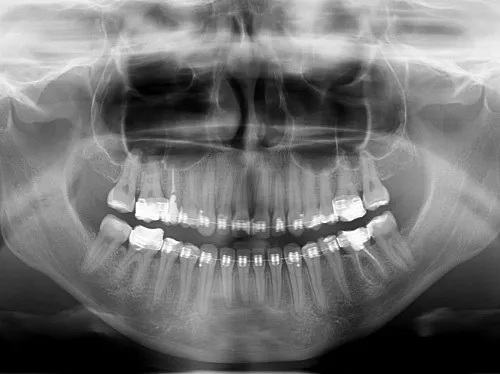

- Zawsze wymagane jest skierowanie na badania rentgenowskie zębów (RTG, pantomogram, CBCT), zarówno na NFZ, jak i prywatnie.

RTG punktowe, pantomogram, tomografia (CBCT): Bezpieczeństwo i przepisy prawa

To bardzo ważna kwestia, na którą zawsze zwracam uwagę moim pacjentom. Niezależnie od tego, czy korzystasz z usług na NFZ, czy prywatnie, na wykonanie jakichkolwiek zdjęć rentgenowskich czy to małego RTG punktowego, dużego pantomogramu (zdjęcia panoramicznego), czy zaawansowanej tomografii komputerowej (CBCT) zawsze potrzebne jest skierowanie od lekarza dentysty. Wynika to z przepisów prawa atomowego i troski o bezpieczeństwo pacjenta. Promieniowanie rentgenowskie jest dawką, którą należy stosować z umiarem i tylko wtedy, gdy jest to medycznie uzasadnione. Skierowanie jest gwarancją, że badanie jest niezbędne dla prawidłowej diagnozy i planu leczenia.

Kto może wystawić skierowanie na prześwietlenie zębów?

Skierowanie na badania rentgenowskie zębów, takie jak RTG punktowe, pantomogram czy tomografia, może wystawić wyłącznie lekarz dentysta. To on, po zbadaniu pacjenta, ocenia, jakie badanie obrazowe jest potrzebne do postawienia diagnozy i zaplanowania leczenia.